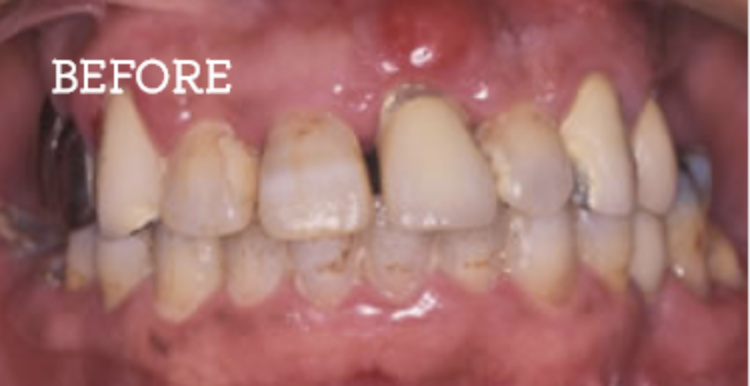

お困りごとを参考に、治療のbefore・afterが確認できます。治療過程や期間、費用などを参考にご覧ください。